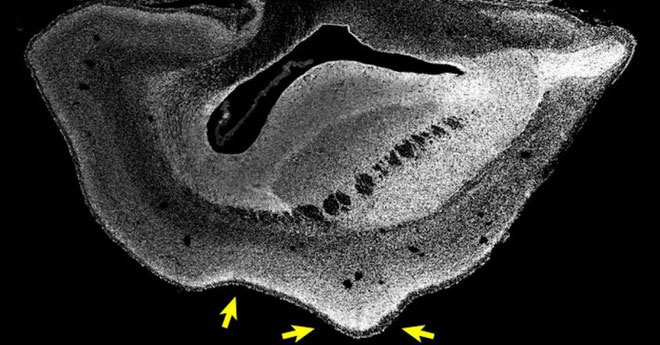

Hình bên trái là não thường, bên phải là não được tăng kích cỡ do tác động của gene.

- Tăng kích thước bộ phận tân vỏ não (neucortex) của khỉ.

- Não xuất hiện nếp gấp tương tự như não người.

- Số lượng loại tế bào liên quan tới sản sinh neuron tăng lên.

- Đặc biệt, gene làm tăng số lượng neuro ở lớp ngoài của não, chính là những neuron đã xuất hiện nhiều hơn dọc chặng đường tiến hóa.

Bào thai khỉ với kích cỡ não tăng.